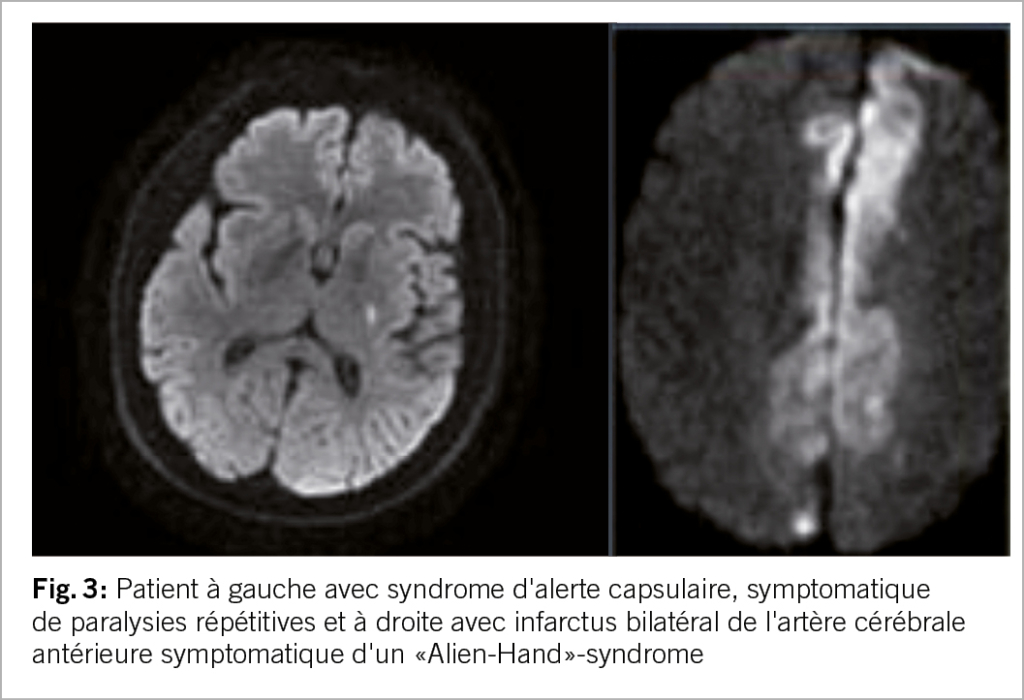

Ces mouvements peuvent être des secousses rythmiques en forme de crise, parfois accompagnées de contractions musculaires toniques prolongées. Les AIT (accidents ischémiques transitoires) de type limb shaking se manifestent par des mouvements rythmiques, involontaires et saccadés des membres dus à une sténose sévère de l’ artère carotide interne. Ces AIT hémodynamiques peuvent être déclenchées par une diminution du débit sanguin cérébral, par exemple lors d’un changement de position ou d’un effort physique, et peuvent être confondues avec des crises d’épilepsie focales. Le syndrome de la main étrangère est défini comme un mouvement involontaire et incontrôlable, mais apparemment ciblé, d’un membre supérieur. En cas d’ infarctus dans la région du corps calleux, différents comportements moteurs anormaux et involontaires peuvent se produire (12) (fig. 3).